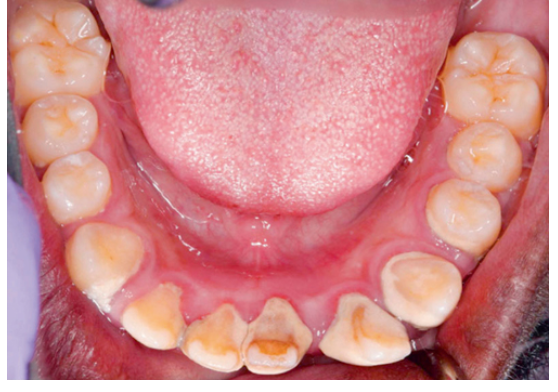

<p>50. What terminology would you use to describe the location of tooth #24 seen in Fig. 5.31?</p><p>a. Torsiversion</p><p>b. Infraocclusion</p><p>c. Labioversion</p><p>d. Linguoversion</p>

50. What terminology would you use to describe the location of tooth #24 seen in Fig. 5.31?

c. Labioversion